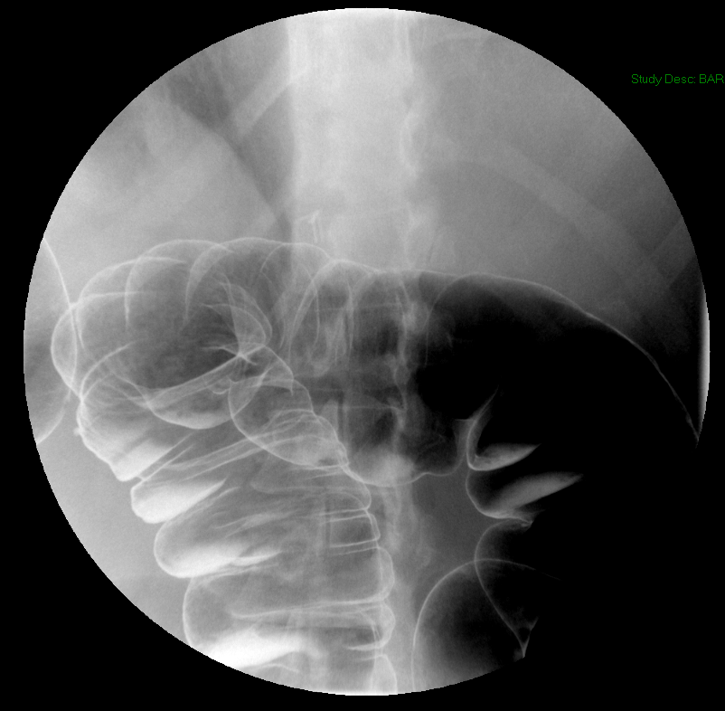

- Method—Thoracic:

- With the patient standing upright, have them turn into a left posterior oblique position.

- Instruct the patient that you will be handing them a cup containing a small amount of water and effevescent crystals and that they should drink it as quickly ask possible.

- As soon as the patietn has finished the water, exchange the empty cup for a cup of thick barium.

- Ask the patient to drink two (2) sips of thick barium. The patient does not need to drink this quickly.

- After the patient has begun drinking, take images of the upper and lower esophagus distended and coated with barium

(key image 5)

(key image 6)

(key image 7).

- Have the patient turn into the right posterior oblique position.

- Repeat steps 3 and 4, only this time the patient will take the barium in their right hand

(key image 8)

(key image 9)

(key image 10).

- Thoracic images are obtained in the upright RPO and LPO projections after the adminstration of bubbly barium (EZ Gas followed by thick barium).

- The goal of these images is to see the thoracic esophagus distended and coated with barium. This may not be possible with one image and make take several to accomplish.